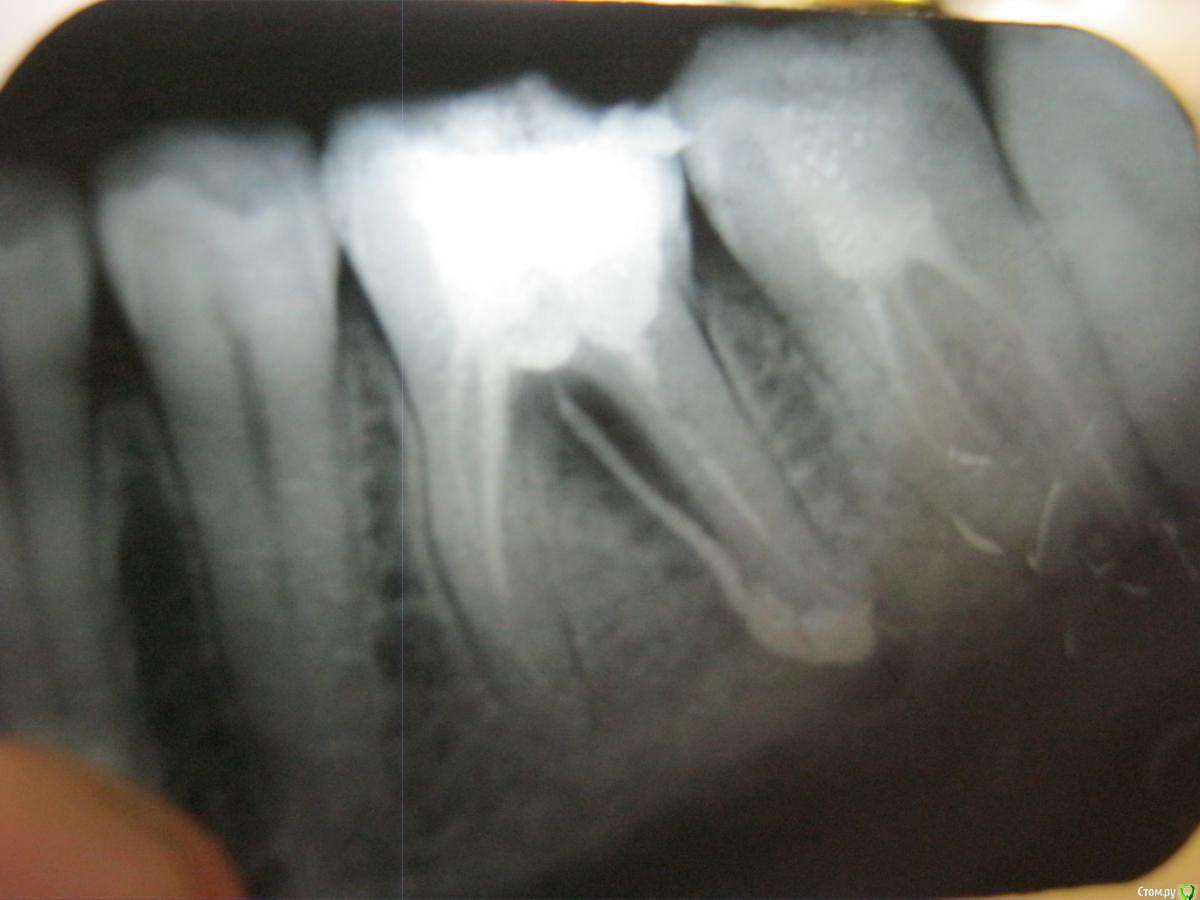

Евгения82 Опубликовано 17 ноября, 2015 Поделиться Опубликовано 17 ноября, 2015 В начале зимы 2014 г. мне пролечили зуб с удалением нерва. Он начал меня беспокоить и как оказалось в нем плохо были запломбированы каналы и остался обломок иголки (на фото в канале справа). На последнем снимке видно воспаление и какое-то образование посредине.Знакомая врач не говорит правду, чтобы меня не расстраивать. Подскажите чем это грозит в дальнейшем.Прикрепляю последний снимок с уже перезапломбироваными каналами Ссылка на комментарий

Гарриевич Опубликовано 18 ноября, 2015 Поделиться Опубликовано 18 ноября, 2015 Зуб на удаление, сосед справа на перелечивание Ссылка на комментарий